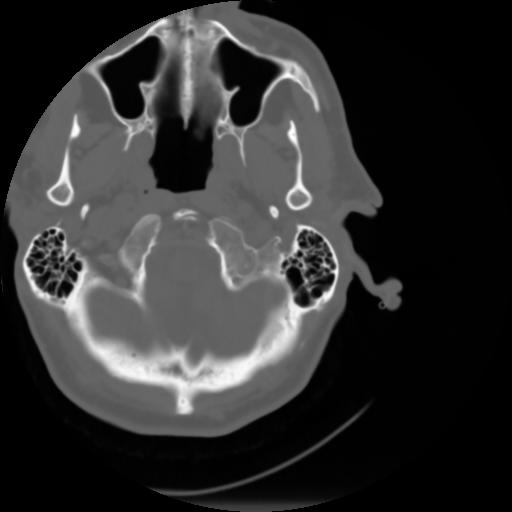

3 CEREBRO,,Axial,3.0,CEREBRO,,